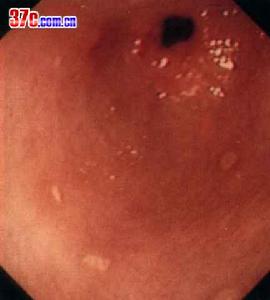

2、胃鏡檢查和黏膜活檢胃鏡檢查不僅可對胃十二指腸黏膜直接觀察、攝影,還可在直視下取活檢作病理和Hp檢測。它對消化性潰瘍的診斷和良、惡性潰瘍鑑別診斷的準備性高於X線鋇餐檢查。在潰瘍太小或太表淺,鋇餐檢查難以發現;鋇餐檢查發現的十二指腸球部畸形可有多種解釋難以確診;活動性上消化道出血是鋇餐檢查的禁忌證,內鏡檢查可確定其來源和性質。鋇餐檢查或內鏡下看似良性的GU中,大約5%實際是惡性的,反之少部分看似惡性的潰瘍,事實證明是良性的,不作活檢難以鑑別。此外,內鏡檢查還可發現伴隨潰瘍的胃炎和十二指腸炎。內鏡下消化性潰瘍多呈圓形或橢圓形,偶也呈線狀,邊緣光整,底部充滿灰黃色或白色滲出物,周圍黏膜可有充血、水腫,有時見皺襞向潰瘍集中。內鏡下潰瘍可分為活動期(A)、癒合期(H)和瘢痕期(S)三個病期,其中每一病期又可分為1和2兩個階段。